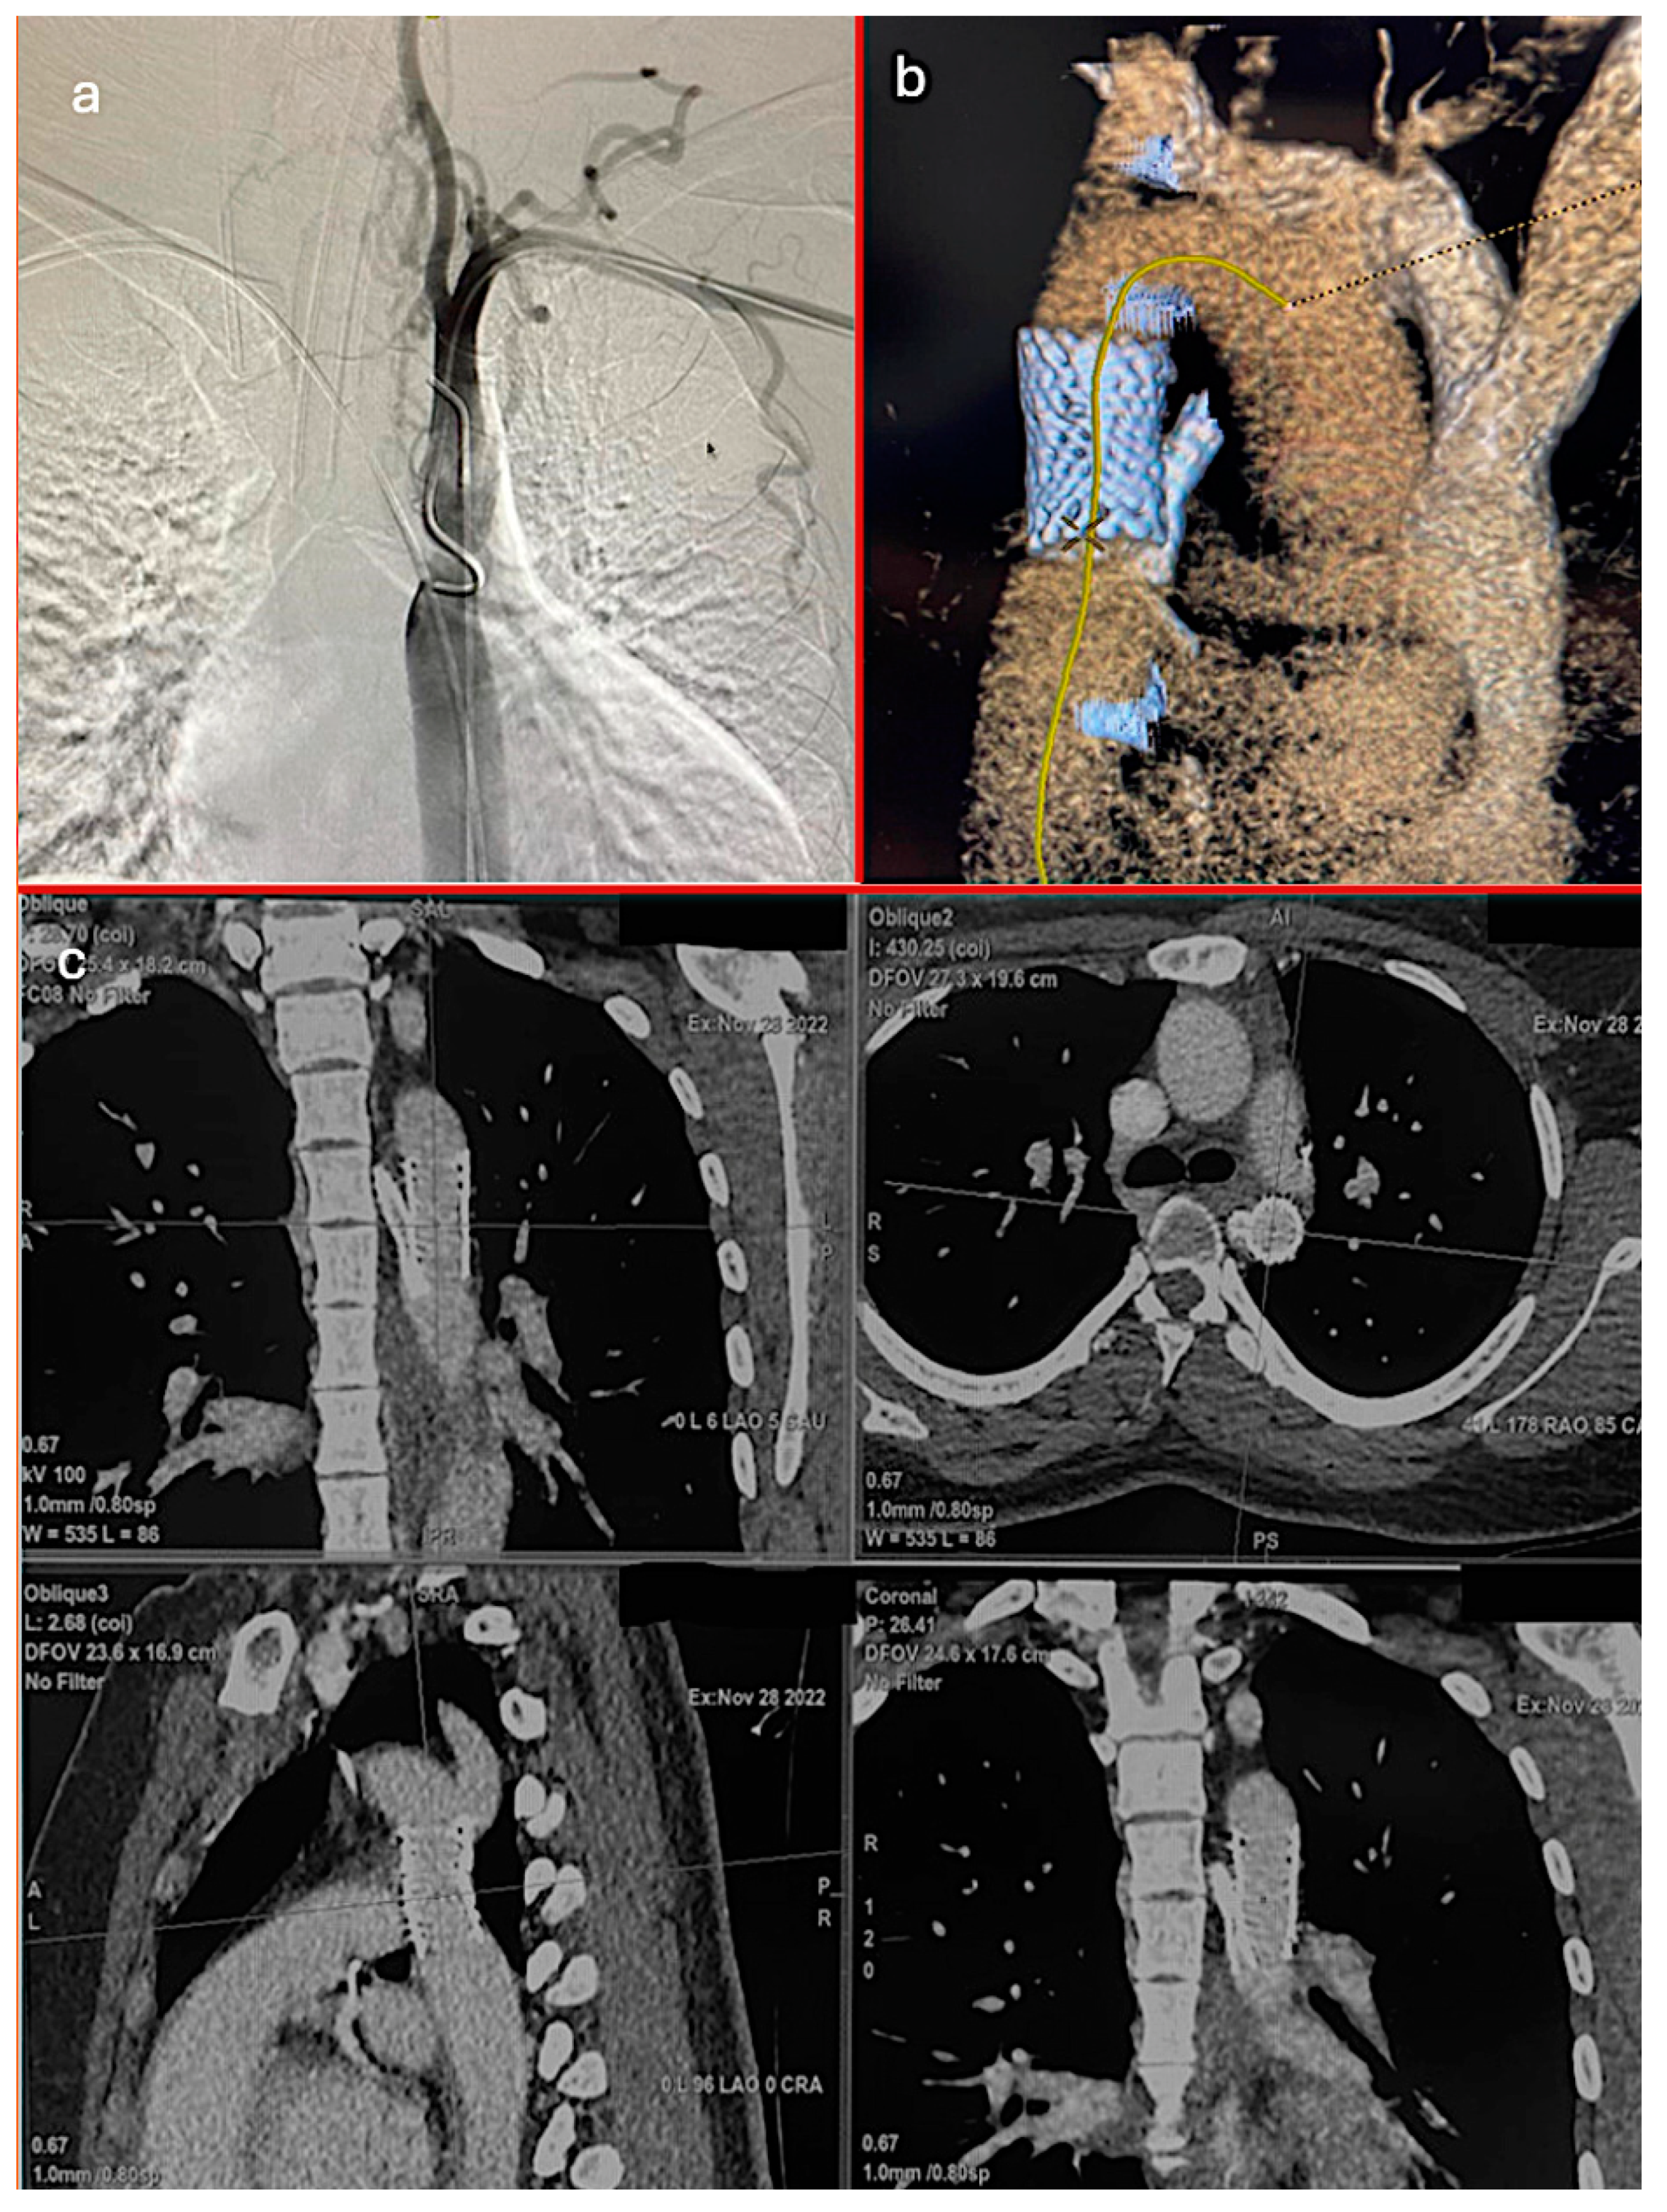

Regarding the timing of the interventions, 67 patients (97.1%) underwent elective repairs, and 2 (2.9%) required emergent procedures. The repair techniques included endovascular treatment in 17 patients (24.6%), surgical end-to-end anastomosis in 33 patients (47.8%), and surgical patchplasty in 19 patients (27.5%). Figure 1 provides a detailed visualization of the aortic coarctation case in one of our patients. The postoperative CT scan confirmed the proper positioning of the aortic graft and chimney ARSA stent, illustrating the favorable outcome of the surgical intervention (Table 1, Graph 1, Figure 2).

Figure 2.

(a) Preoperative angiography of coarctation, (b) postoperative 3D CT imaging of aortic graft and chimney ARSA stent, (c) postoperative CT imaging of aortic graft and chimney ARSA stent.